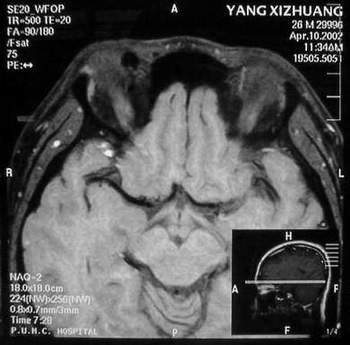

MRI及增强结果如下:

患者压颈及其它Valsava试验结果阴性。从MRI分析,在T1、T2、T+C检查该支血管均为明显流空现象,说明该血管血流速度很快,而从走行和分布看,眼上静脉可能性很大。也许也不能除外异常的眼动脉或异常血管。眶内主要可能的血管病变包括颈内动脉海绵窦瘘(高流窦)、AVM、眼眶静脉曲张、海绵状血管瘤、静脉性血管瘤、毛细血管瘤和眶内动脉瘤。。

1、颈内动脉海绵窦瘘:该患者临床有一部分支持该诊断。但从影像分析,海绵窦未见明显扩张;眼外肌未见明显充血扩张的长T1、长T2信号;颈内动脉海绵窦瘘常可见继发到血栓,可见到短T1、长T2的血栓信号。

2、眼眶静脉曲张:该疾患一般常见于小儿。该患大多数会出现Valsava试验阳性,间歇性突眼。不符合该患。影像学检查,于曲张静脉内常可见血栓和静脉石。所以不符合该患。

3、AVM:患者目前的影像学资料尚不全面,但可符合该诊断。临床上改病常见于30岁左右年轻人,单侧发病,于本患较符合。问题在于临床没有明确的血管杂音,似乎难以解释。

4、该患影像学与海绵状血管瘤差别很大,所以可基本排除此诊断。

5、静脉性血管瘤和毛细血管瘤:MRI中等T1、长T2信号,较易与本病鉴别。

6、眶内动脉瘤:我觉得患者并不能排除本病,但同样,由于波动性阴性,似乎也难以解释。

纵上所述:本人觉得,患者AVM可能性较大,同时不能除外眶内动脉瘤。